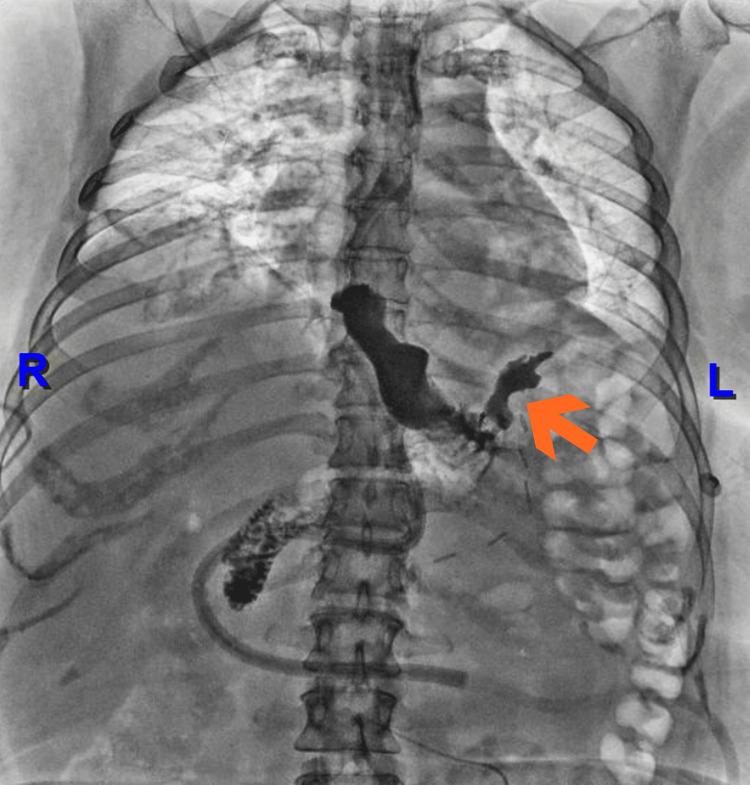

Esophagogastric fistulas are a rare but serious complication after sleeve gastrectomy. Their management remains a clinical challenge, especially when conventional endoscopic approaches, such as stent placement, fail. We report the case of a 49-year-old female with a history of hypothyroidism, major depressive disorder, body mass index greater than 50 kg/m², significant smoking history, and obstructive sleep apnea, who developed acute abdominal pain and bleeding after laparoscopic sleeve gastrectomy. She was referred to our institution in hypovolemic shock and underwent exploratory laparotomy with abdominal packing. An upper endoscopy revealed a 5-10 mm esophagogastric leak initially managed with a covered self-expanding stent, which subsequently migrated. The persistent fistula was confirmed by contrast study, and endoscopic negative pressure therapy (endoscopic vacuum-assisted closure (EndoVAC)) was initiated using a polyurethane sponge with scheduled replacements. After six sessions, complete fistula closure was achieved, confirmed by endoscopic and radiographic evaluation. This case highlights the successful use of EndoVAC therapy as a minimally invasive and effective option for managing refractory post-bariatric esophagogastric fistulas. Early consideration of this technique may improve outcomes in similar scenarios.

食管胃瘘是袖状胃切除术后一种罕见但严重的并发症。其治疗仍然是一项临床挑战,尤其是当传统的内镜治疗方法(如支架置入)失败时。我们报告一例49岁女性病例,该患者有甲状腺功能减退、重度抑郁症病史,体重指数大于50kg/m²,有大量吸烟史及阻塞性睡眠呼吸暂停,在腹腔镜袖状胃切除术后出现急性腹痛和出血。她因低血容量性休克被转诊至我院,接受了剖腹探查并进行腹腔填塞。上消化道内镜检查发现一个5 - 10毫米的食管胃瘘,最初采用覆膜自膨式支架治疗,但支架随后移位。通过造影检查证实存在持续性瘘,遂开始使用聚氨酯海绵进行内镜负压治疗(内镜真空辅助闭合术(EndoVAC))并定期更换。经过六次治疗后,通过内镜和影像学评估证实瘘完全闭合。该病例突出了EndoVAC治疗作为一种微创且有效的方法成功用于处理减重术后难治性食管胃瘘。在类似情况下,早期考虑这种技术可能会改善治疗效果。